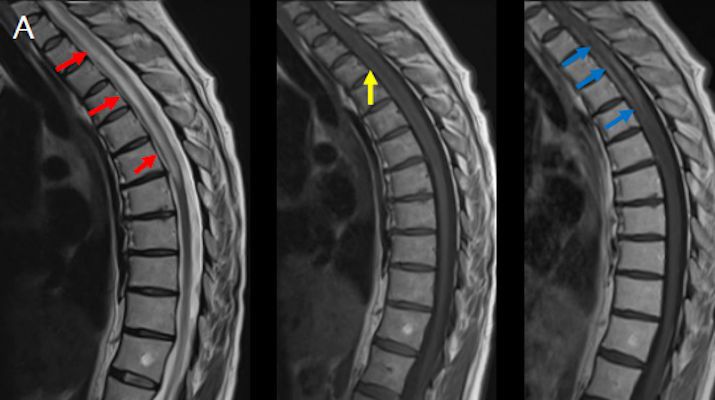

- (A) Torakal MRG’de sagital görüntülerde üst-orta torakal düzeyde T2A hiperintens (oklar), T1A izo-hipointens (ok) uzun segment ekspansil sinyal değişikliği izlenmekte olup sagital postkontrast T1A’da kontrast tutulumu mevcuttur (oklar). Bulgular longitudinal ekstensif transvers miyelit (LETM) ile uyumludur.

- Transvers miyelit sıklıkla santral gri cevheri etkileyen ve üç veya daha fazla vertebral gövde uzunluğunu etkilemektedir (LETM).

- Transvers kesitlerde, santral kordu tutma eğilimindedir.

- Omurilik atrofisi ve ekspansiyon/ödem MS’e göre daha fazla görülür.

- Kontrast madde enjeksiyonu sonrasında neredeyse tüm akut NMO lezyonları, yamalı, düzensiz veya periferik olarak kontrastlanma gösterir.